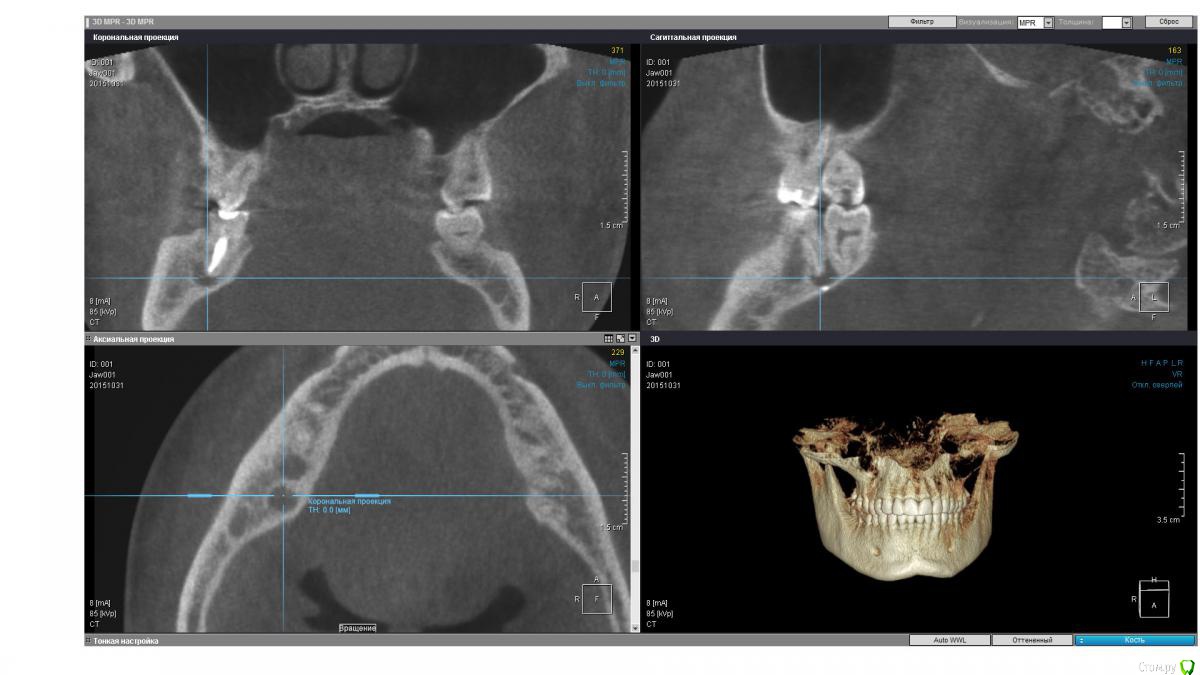

isubru Опубликовано 31 октября, 2015 Поделиться Опубликовано 31 октября, 2015 (изменено) Здравствуйте, Депульпировали зуб, потом он болел где-то с год. Больно было сильно надкусывать, потом боль прошла. "Смеркалось". Через какое-то время на десне сформировался "гноепровод". Постоянно что-то течет. Зуб предлагают удалять (должен сказать, что эта процедура настолько тут в ходу, что на неё всех поголовно отправляют). Сделал КТ. Под 47 действительно 2 кисты, но что интересно на дне полостей какие-то плотные нитевидные "обломки" в 2.5-2.8мм длинной и 1мм в диаметре. Буду очень признателен совету, как мне избавится от этой напасти. Зуб, видимо, уже не спасити?31 ноября 2015 Чуть менее годом ранее. Изменено 31 октября, 2015 пользователем isubru Ссылка на комментарий

DmitrySH Опубликовано 31 октября, 2015 Поделиться Опубликовано 31 октября, 2015 Если только на основании данного КТ, то есть шансы и спасти.На КТ фрагментов инструмента не увидел. Есть какие-то точки. Но надо понимать, что пломбировочным материал, инструменты и тп в каналах сильно "фонят" на КТ. Прицельные снимки есть? Ссылка на комментарий

isubru Опубликовано 31 октября, 2015 Автор Поделиться Опубликовано 31 октября, 2015 (изменено) Да, был. Нужно поискать. Только там в принципе тоже самое. Одна киста, что между 46 и 47 слабо различима в той проекции, хорошо видно только ту, что под другим корнем. PS. Прикрепил в 1й пост. Относительно точек, вряд ли это артефакт (только 2 специфических места на всей CT). Да и на прицельном снимке они есть. Какова вероятность, что они могли быть причиной образования кист(к примеру, механическое повреждение ими при надкусывании на этом зубе)? Изменено 31 октября, 2015 пользователем isubru Ссылка на комментарий